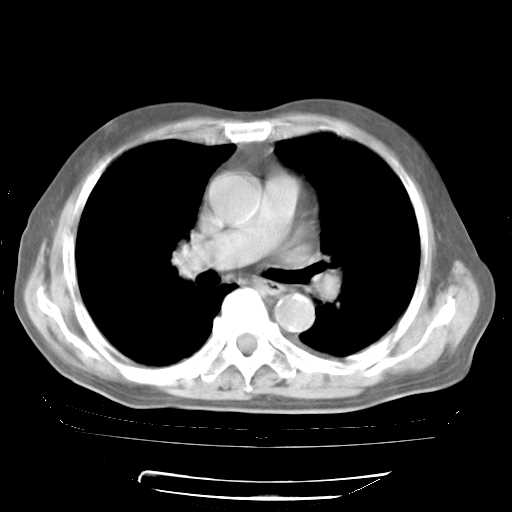

4月28日肺部CT——再次出现类似去年5月9日——透光度降低,“间质性”改变。

4月28日肺部CT——再次出现类似去年5月9日——磨玻璃样、间有“粟粒样”改变。

4月28日肺部CT